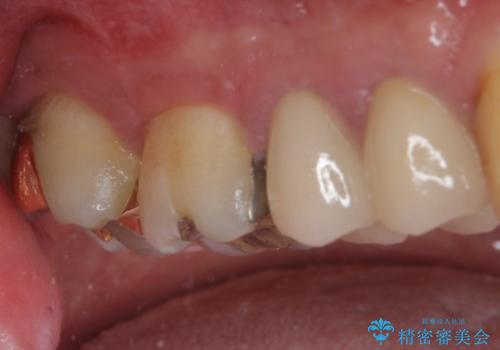

ゴールドインレーは銀歯のインレーやセラミックインレーと比べ、「技工操作の精度が高く、適合が著しく良い」というメリットがあります。特に上の奥歯は歯科医師の操作が行いにくいため、「適合の良さ」は再治療のリスクを防ぐ上でとても重要な要素となります。

上の奥歯は金属色が見えることもないため、審美的な問題は全くありません。

咬み心地はとても良好で、全く違和感がなく、患者様には大変満足していただきました。